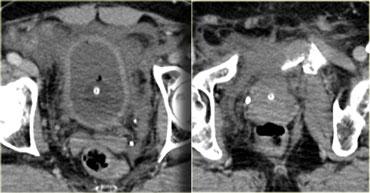

Bên trái là hình ảnh trước và sau khi chụp CT bàng quang cản quang.

Có thuốc cản quang trong lòng bàng quang bao quanh ống thông Foley và có hiện tượng thoát thuốc cản quang vào khoang trước bàng quang hay khoang Retzius.

Hình ảnh này được gọi là ‘dấu hiệu răng hàm’ (molar tooth sign), gợi ý vỡ bàng quang ngoài phúc mạc.

Bên trái là tái tạo mặt phẳng đứng dọc và đứng ngang.

Lưu ý không có thuốc cản quang lan vào rãnh cạnh đại tràng, do đó không có sự lan rộng vào trong phúc mạc.